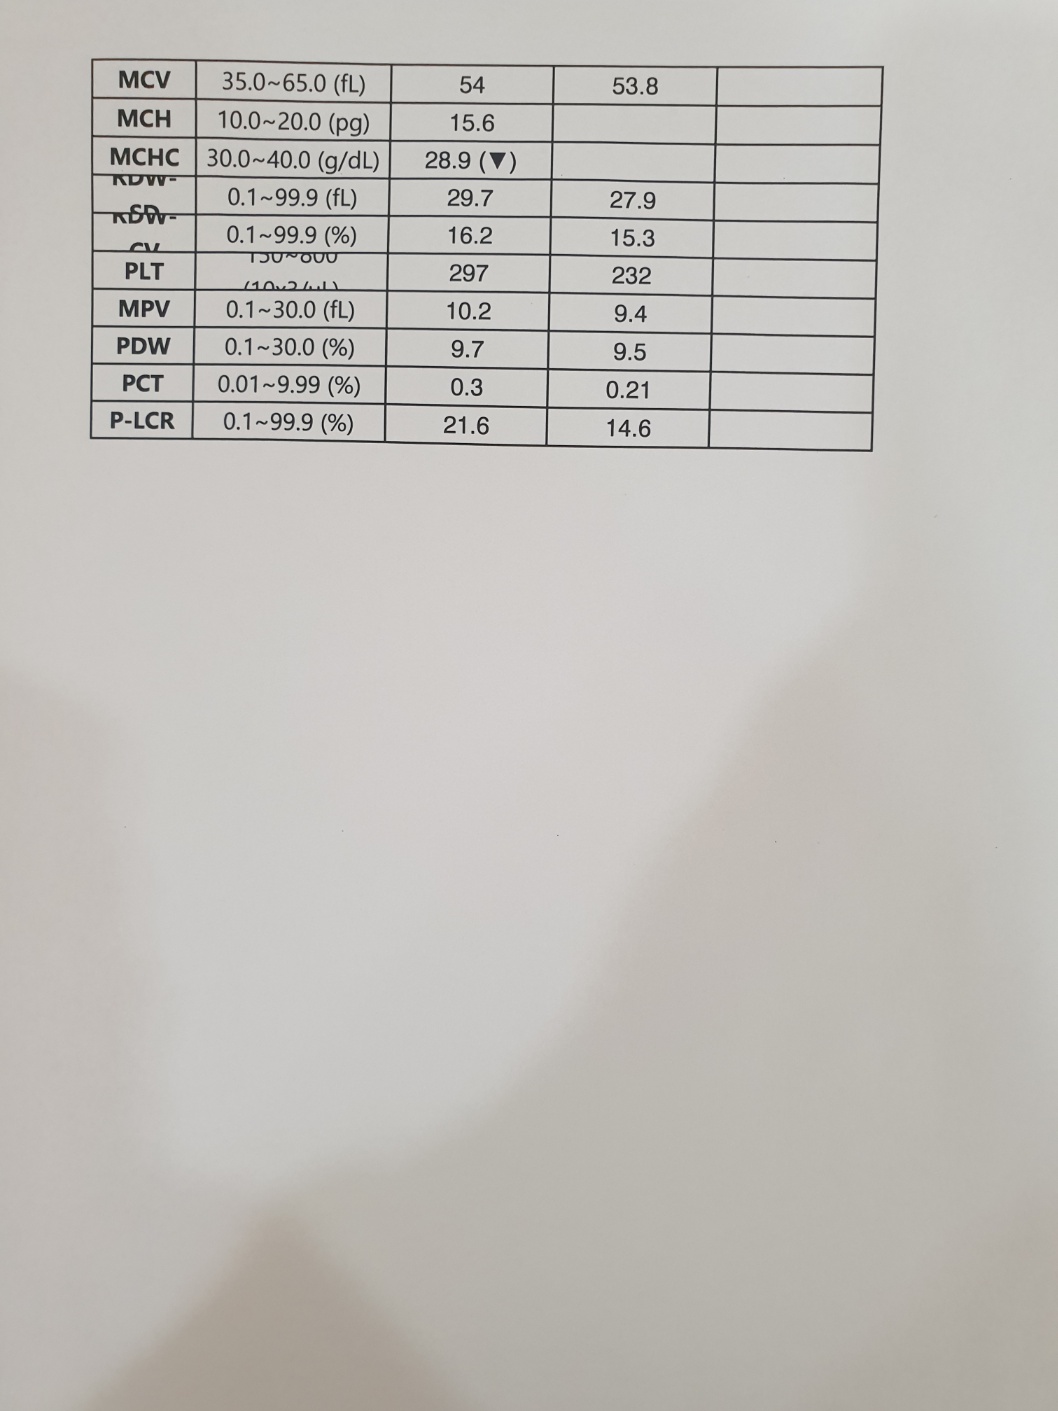

| 치료과정 | 2024년 12월 7일 토요일 오전에 피침을 흘리며 기력 없이 쓰러져 있던 동경이는 바로 병원으로 이동했습니다.. 12월 초부터 이상 징후가 있었던 동경이를 지켜보면서 혹시나 범백이 아닐까 의심스러웠던지라 의사 선생님께 그동안의 상황을 설명하고 범백키트 검사를 먼저 하였습니다.. 너무나도 다행스럽게 범백은 음성으로 나왔습니다 그동안 만약 범백이라면 밥자리에 있는 많은 아이들은 어쩌나 싶어서 정말 걱정이 되었거든요 너무 너무 다행스런 순간이었습니다.. 이후 엑스레이와 혈액검사를 진행 하였고 엑스레이 결과 위장 내용물이 한개도 없었다는..ㅠ ㅠ 그동안 전혀 먹지를 못했다는 것이었지요 얼마나 아프고 힘들었을지 .. 동경이 한테 너무 미안 했습니다 며칠이라도 빨리 병원에 데리고 왔으면 덜 고생 했을텐데.. 미안하고 또 미안 했어요 .. 모든 검사결과 신장이 거의 두배로 부어있었고 혈액검사도 신장수치와 췌장수치를 포함한 모든 수치가 많이 높게 나왔습니다 선생님께서 급성신부전으로 진단하시고 바로 수액처치와 필요한 치료에 들어갔습니다.. 입원 이틀동안은 자발식이가 전혀 없어서 걱정스러웠는데 삼일째 드디어 동경이가 먹기 시작했습니다.. 입원 삼일째부터 동경이는 그동안 굶은것을 만회 하는것처럼 너무 너무 잘 먹어주었습니다 매일 매일하는 링거치료도 잘 견뎌주고 착한 아이라고 선생님께 칭찬도 많이 받았어요..ㅎㅎ 저를 보면 반가움의 인사가 비록 하악질로 시작 됐지만 잘 이겨내고 서서히 회복해가는 동경이를 얼마나 기쁘고 감사하던지 .. 의사 선생님께서 입원 치료중 중간 시점에 혈액검사를 권하였지만 검사 자체가 동경이 한테 큰 스트레스가 될수 있으니 며칠 더 치료후 검사를 해달라고 했고 드디어 12월 17일 혈액검사를 했습니다.. 피 뽑고 결과를 기다리는데 어찌나 떨리던지 ..ㅠ 검사 결과 동경이의 신장을 포함한 모든 수치가 정상으로 나왔고 퇴원이 가능해졌습니다 |